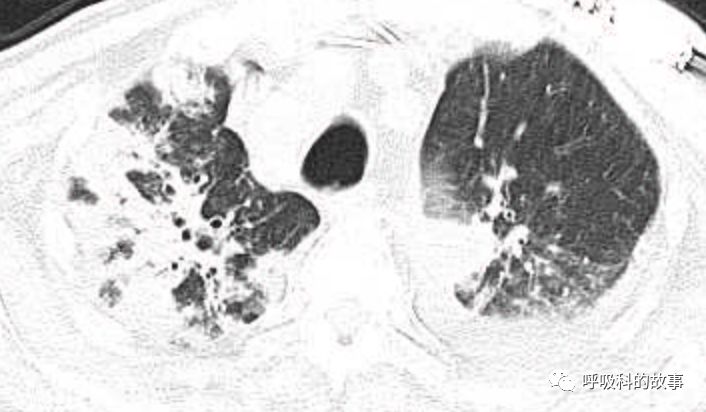

肺部CT如下:

以上的CT给我第一眼的感觉是肺炎,再结合患者有发热和血炎症指标明显增高,肺炎的诊断应该没有问题,但是胸水又是漏出液,结合脑钠肽增高和患者有胸闷气急的症状,心功能不全的诊断也能成立。在某些层面,肺部实变影以内中带为主,还要考虑肺水肿的诊断。入院后给予患者美罗培南抗感染、托拉塞米利尿治疗,以及化痰、雾化处理,患者体温在入院后三天就正常了,入院第五天复查NT-proBNP3390pg/ml;血常规示白细胞 13.5*10^9/L,中性粒细胞81.8%,淋巴细胞13.2%,超敏C-反应蛋白 25mg/L;电解质示钠 160mmol/L,氯 111mmol/L 。虽然炎症指标和心功能指标均有好转,但患者却仍旧精神差,每次查房时仍然表现嗜睡状,家属也反映患者不论白天还是夜晚多数时间不是太清醒。那么问题出在哪里呢?